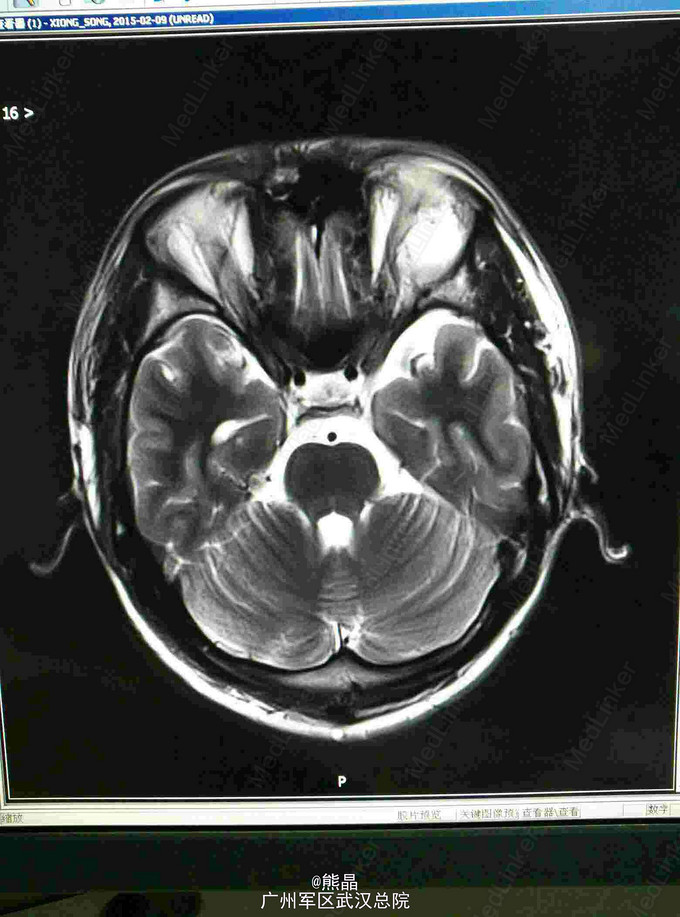

左眼眶神经鞘瘤的MRI表现一例

男性患者,27岁,左眼球突出2月余

MRI表现:左眼眶内球后肌锥内可见一椭圆形等T1长T2信号,内可见液平,增强呈斑片状强化,余未见明显异常

本院手术,术后病理,神经鞘瘤